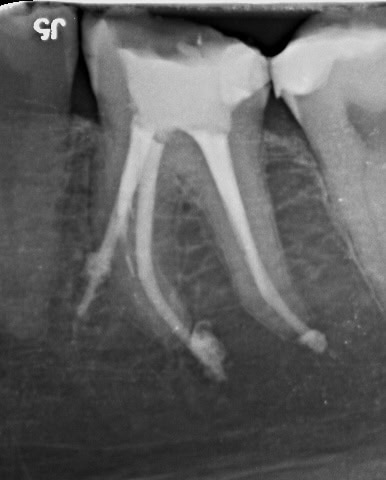

Exemplu: Un premolar doi superior – în mod obișnuit cu un singur canal – a fost tratat de două ori fără succes. Sub microscop s-au identificat trei canale, fapt care explică recidiva. Pe radiografia postoperatorie se observă obturația tridimensională completă a tuturor canalelor și prezența unor puncte albe în treimea rădăcinii, corespunzătoare canalelor colaterale tratate și obturate corect.

Premolarul doi superior, tratat anterior de două ori fără izolare, microscop sau laser, a recidivat. Datorită microscopiei, s-au descoperit trei canale, o raritate (incidență 0,5–1%). Radiografia postoperatorie arată obturația completă tridimensională, inclusiv a canalelor colaterale, realizată cu ajutorul laserului Erbium, care a asigurat curățarea integrală a sistemului endodontic.